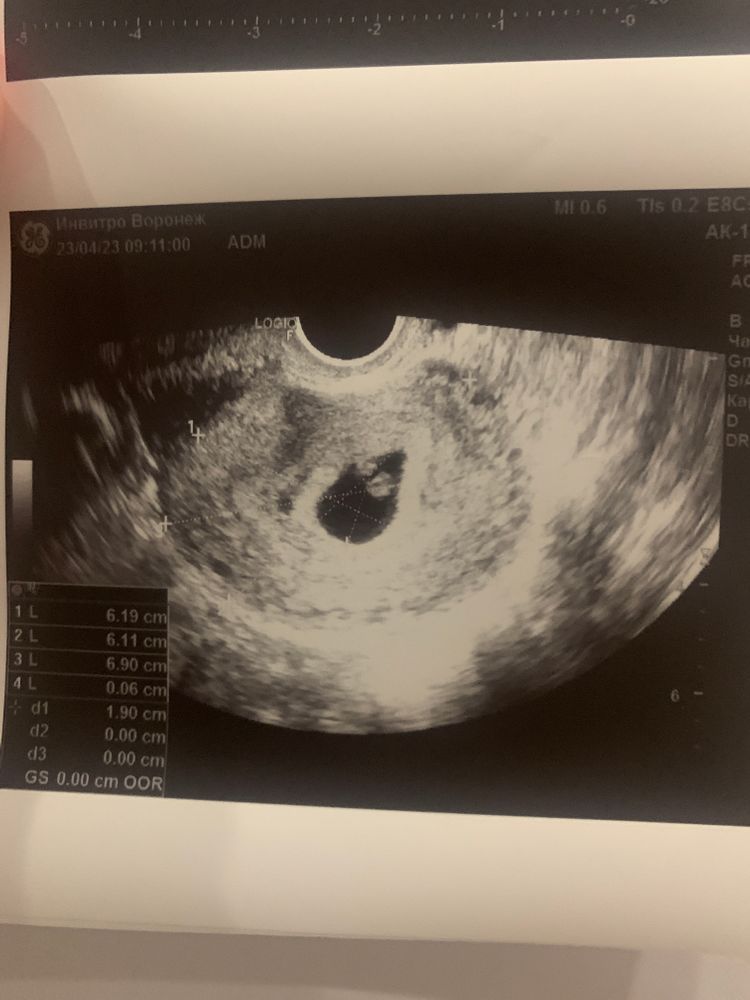

подскажите как быть ?! Стараюсь не думать и сохранять спокойствие , ходила на узи сказали 6.1 неделя , но отсутвует желтого мешочка( дословно не помню ) прописали прогестерон по 10 мг два раза в день - пью ! Сдаю кровь регулярно смотрю динамику хгч в 6.4 недели показатель - 64тыс , в 7 недель - 102 тыс , завтра 7,6 недель почти 8 пойду еще раз сдам на прием только 15 мая , сильный токсикоз ) чем чревато отсутствие желтого (мешочка) ?? Мне сказали что могут быть серьезнейщие патологии развития плода

Так на фото желточный мешочек есть,вы наверное путаете с желтым телом,а это вообще разные вещи

Непонятно о чём речь - о желточном мешочке или жёлтом теле? Скиньте текстовый протокол УЗИ! Там где написано про плодное яйцо и яичники..